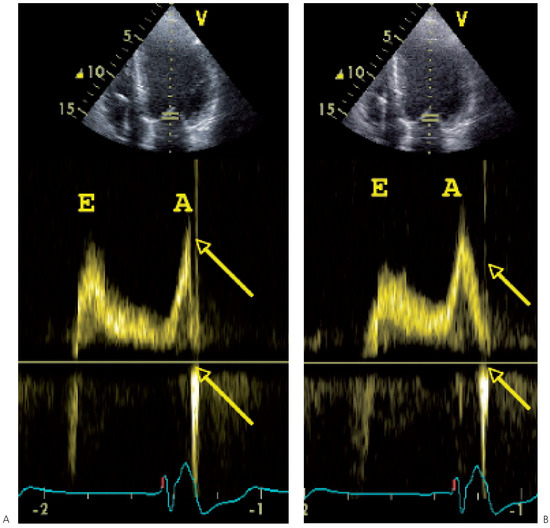

While substantial progress has been made over the past decade in the medical treatment of heart failure, certain patients fail to respond to optimal treatment despite the availability of excellent drugs. Cardiac resynchronisation therapy, or multisit...